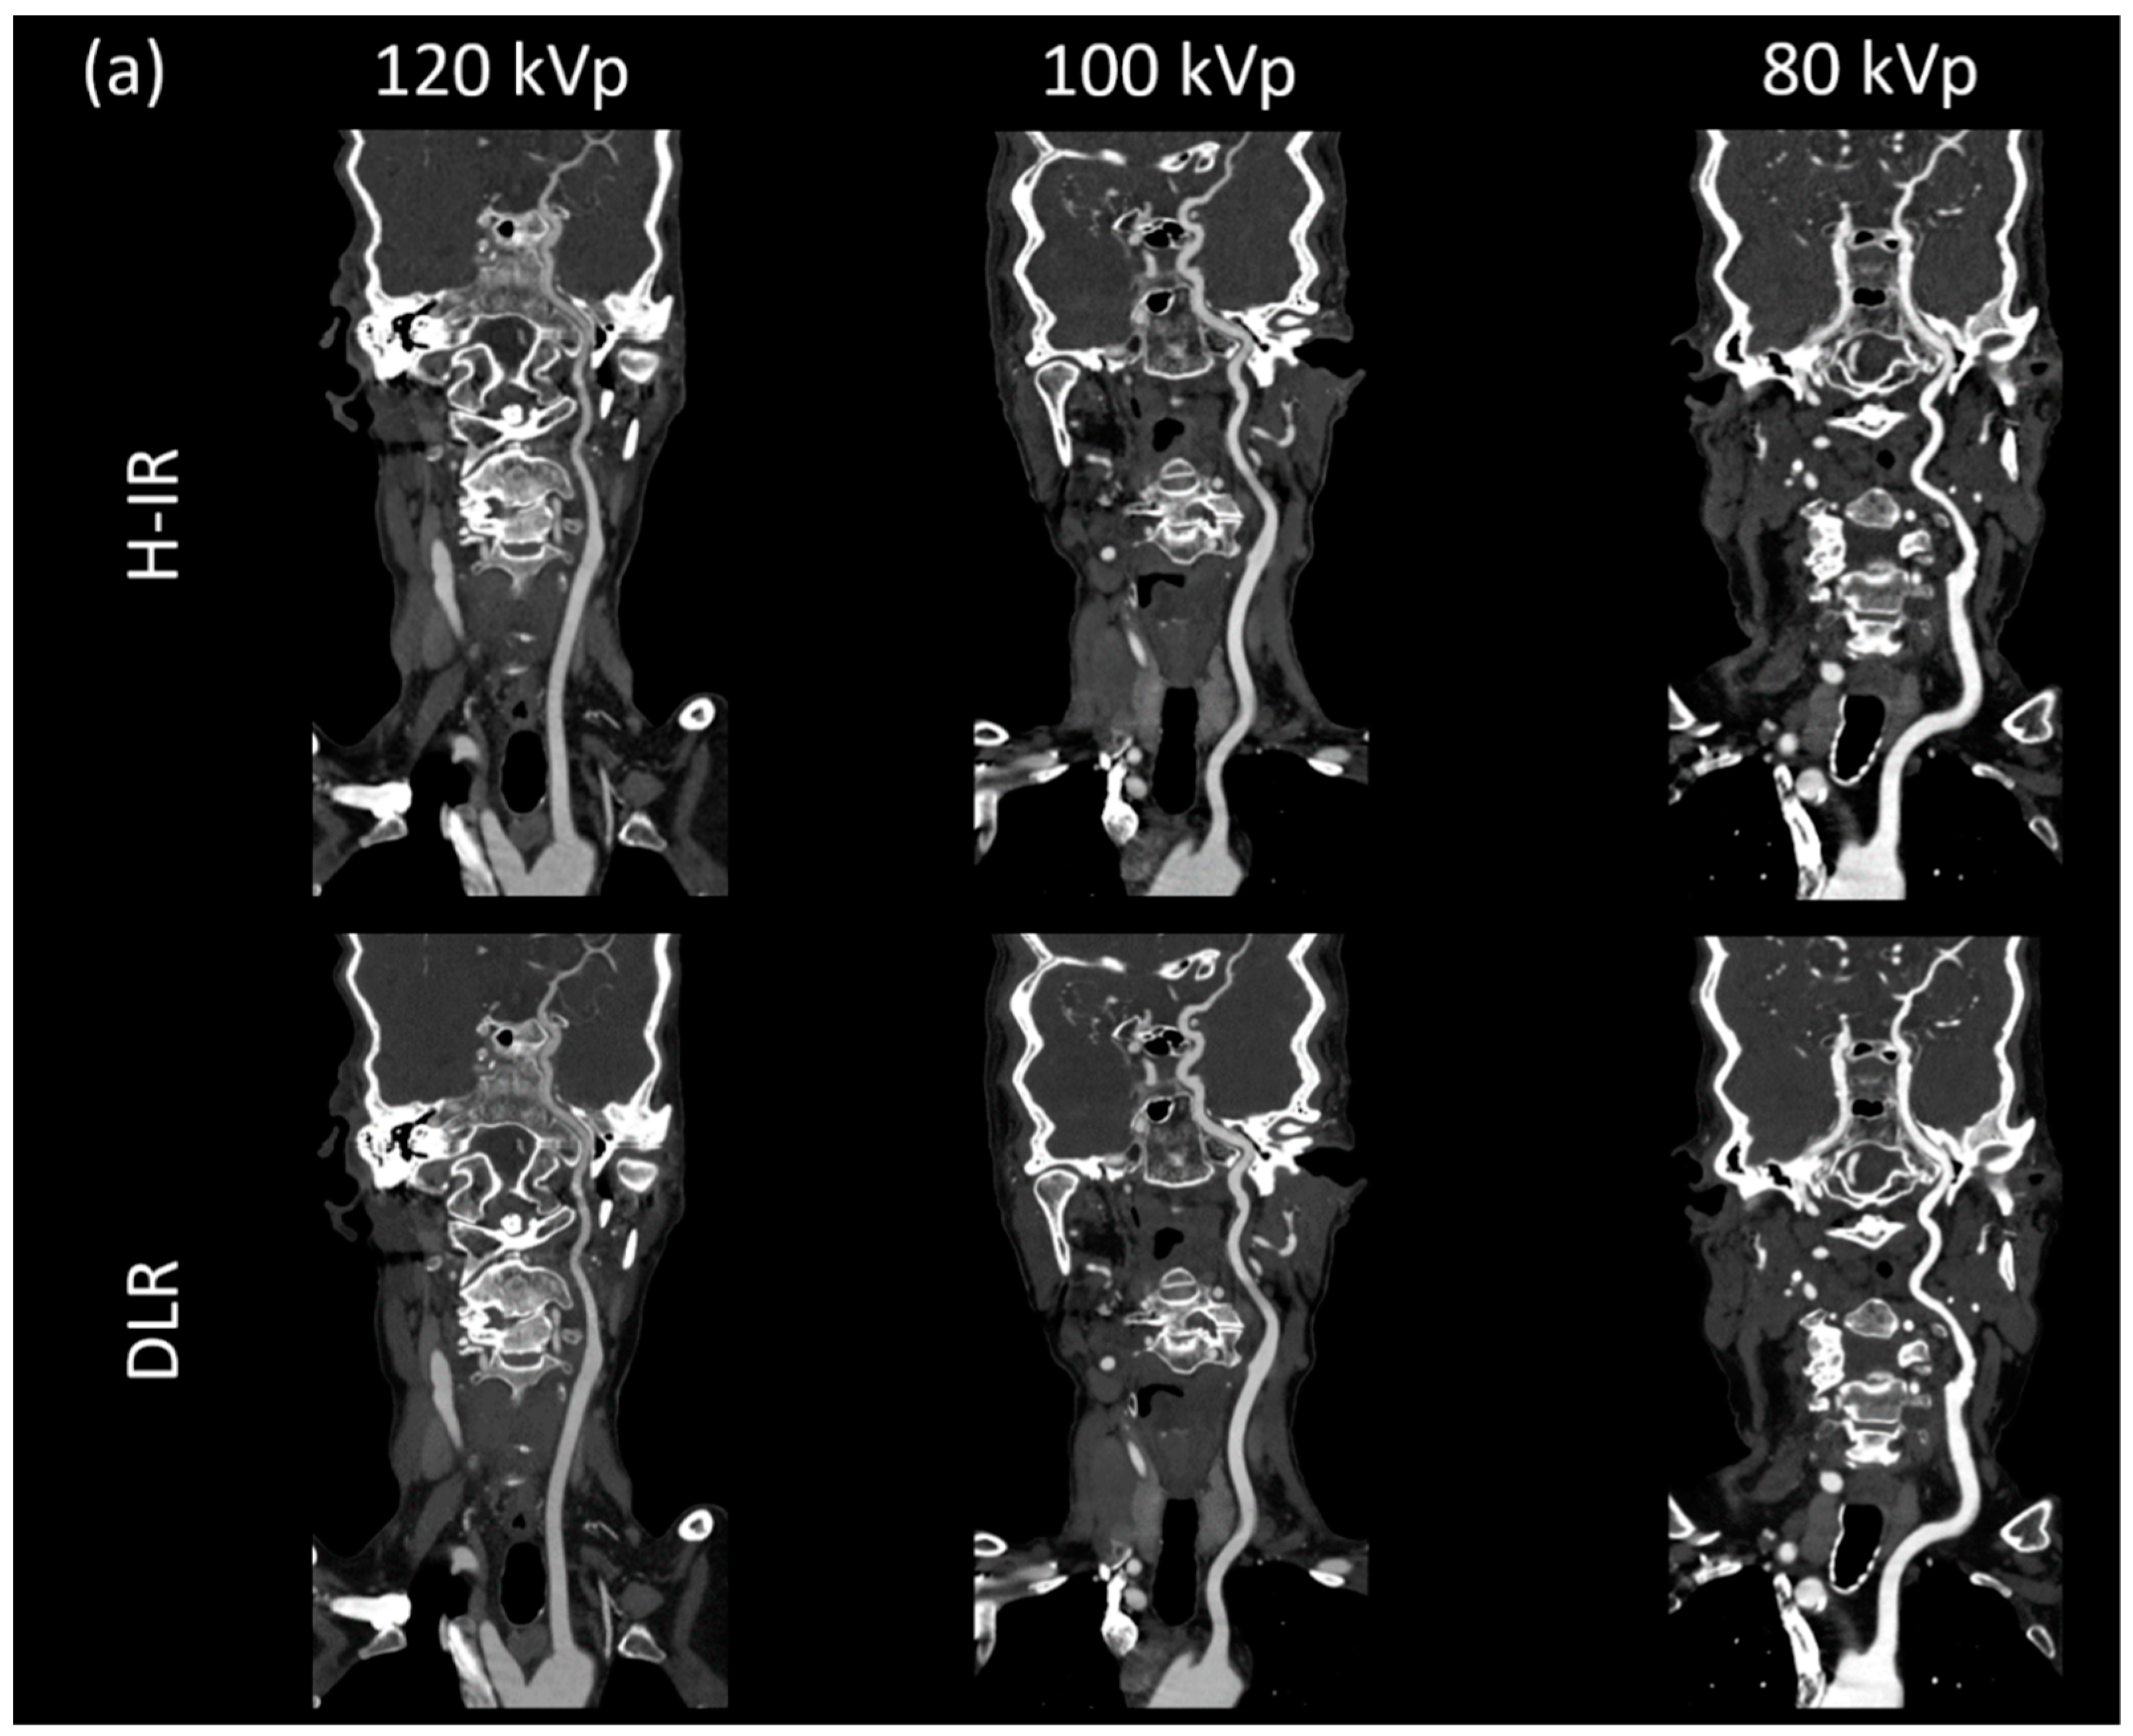

3.3.1. Image Signal Fluctuation with DLR vs. H-IR

3.3.2. Comparison of the Two Reconstruction Techniques at Constant kVp Value

3.3.3. Comparison of Low kVp plus DLR vs. Standard kVp plus DLR

3.3.4. Comparison of Low kVp plus DLR vs. Standard kVp plus H-IR